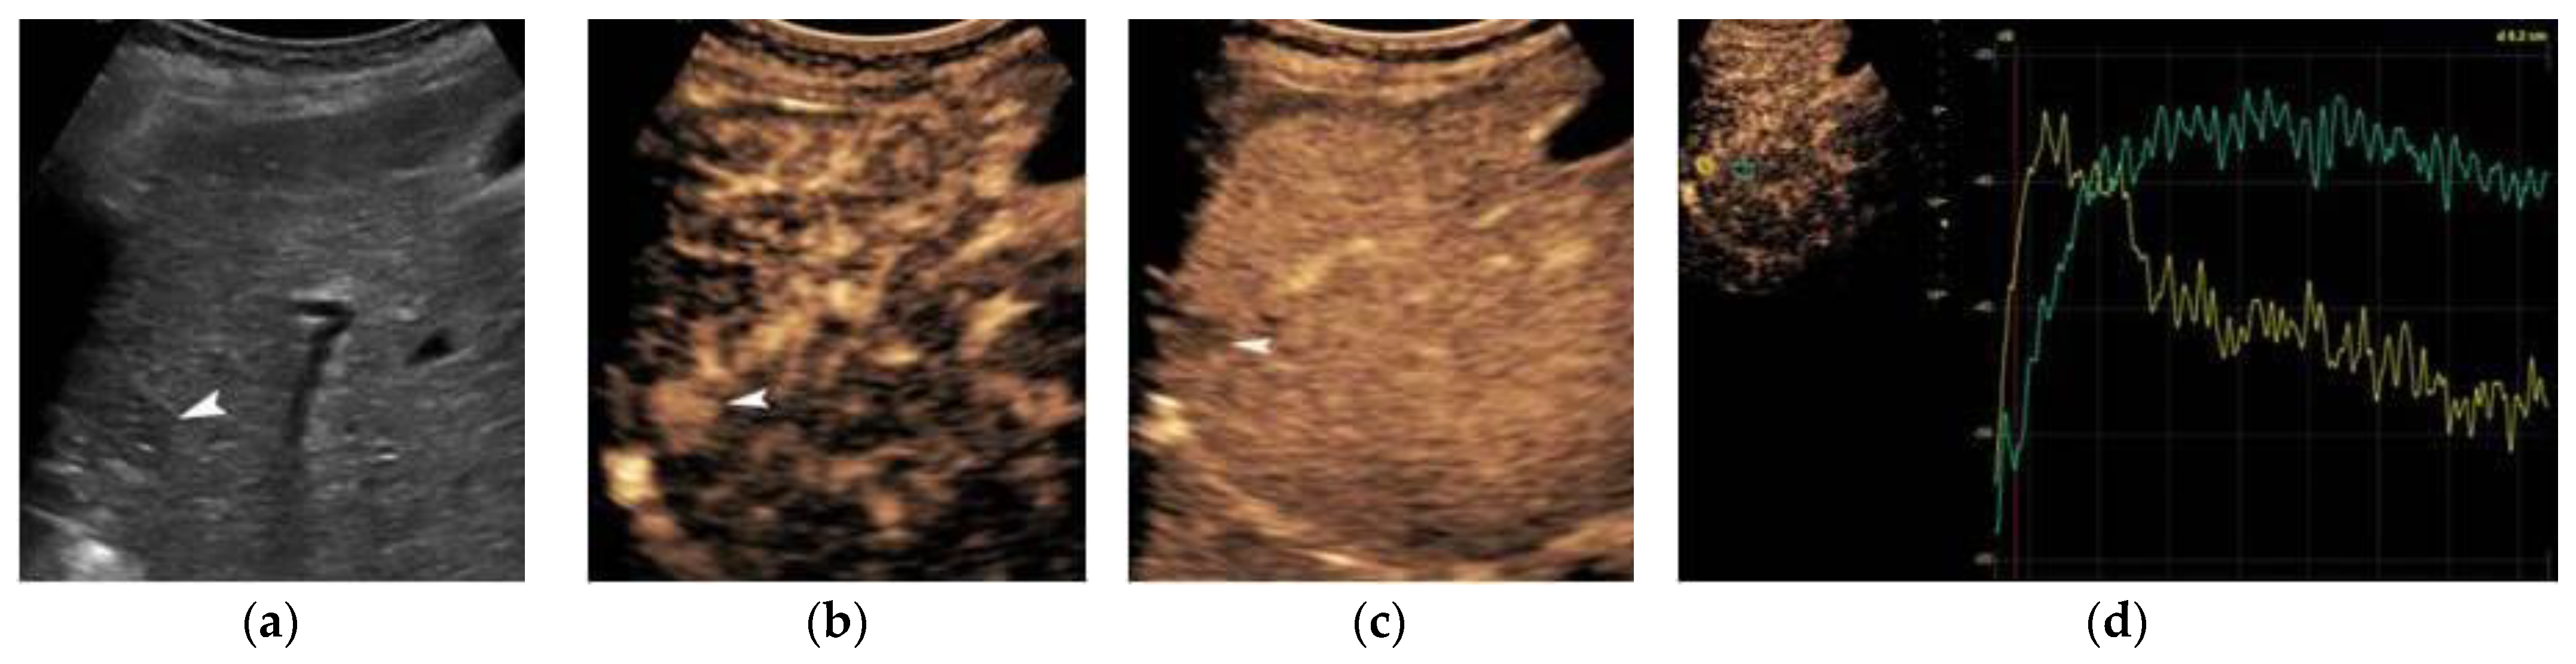

2. Ultrasound

3. Contrast-Enhanced Ultrasound